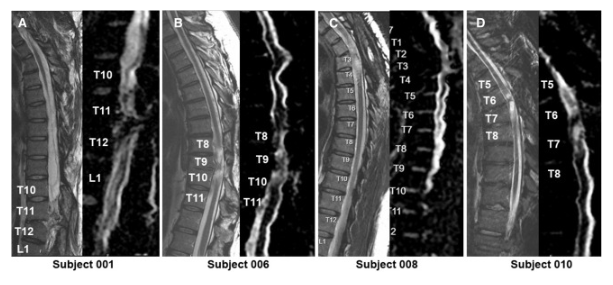

體格檢查顯示兩名患者的神經損傷水平 (NLI)、運動評分和感覺評分均有所改善。與細胞移植兩年后的神經系統評分相比,5 名受試者 001 的改善水平從兩年時的 2 個水平(改善)下降到五年時的?? 1 個水平。受試者 010 的改善在兩年和五年時均保持穩定在 1 個水平的神經系統改善。

通過 MRI 和 DTI 成像評估動態反應

在 NSC 注射后,沒有放射學證據表明出現即時或延遲并發癥,包括術后即時或隨訪成像中沒有出現新的脊髓或軟組織水腫區域、增強或腫脹或積液。在純解剖或擴散張量序列中均未觀察到脊髓脊髓軟化癥的可見形態變化。

在所有四名患者中,彌散張量成像 (DTI) 成像顯示在損傷部位和損傷部位的前端/尾部脊髓束外觀穩定,但未顯示重塑或纖維束造影改善的廣泛證據。